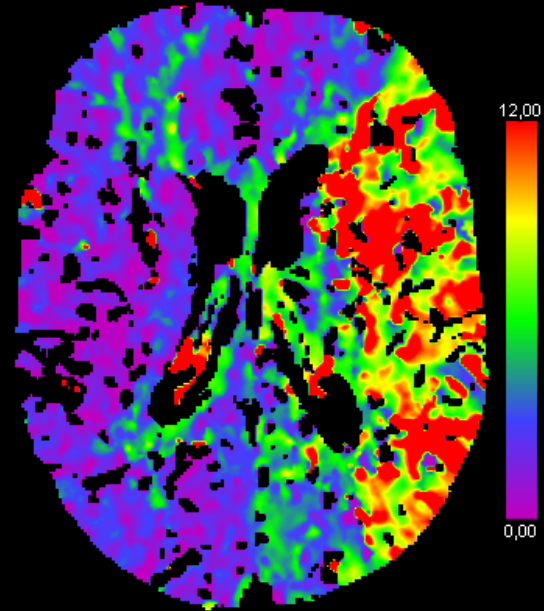

Den tekniske løysinga for betra bildediagnostikk er det Luca Tomasetti som har stått for. Hans del av tvillingprosjektet handla hovudsakleg om å utvikle nye automatiske metodar for bildediagnostikk ved hjelp av maskinlæring. Han har brukt bilete frå CTP-skanning (computertomografiperfusjon) som input for eit såkalla kunstig intelligens-nettverk som kan segmentere områda i hjernen med nedsett blodtilførsel. Med andre ord, skilje ut dei områda i hjernen som bør behandlast.

Forskinga til Tomasetti og Høllesli viser at bruk av bilete basert på CT-perfusjon som input for kunstig intelligens, og i tillegg bruk av nye og meir avanserte parameterar basert på CT-perfusjon, aukar moglegheita for å skilje ut og meir nøyaktig karakterisere dei slagramma områda.